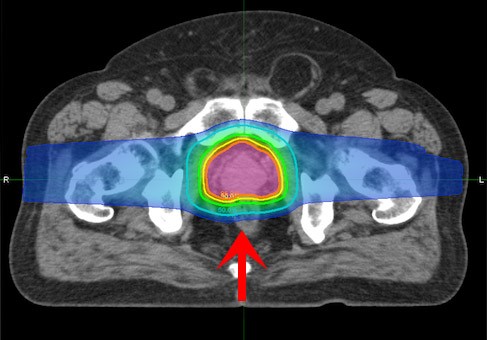

在质子线治疗中,可利用专门的机器和器具,结合Bragg峰的深度和患者不同病灶的形状进行照射。质子放射线进入人体后,能量起初不大,紧接着以光速的60%上升到达峰值(称为布拉格峰),之后又骤降到零——这种优良的剂量分布促使质子束的能量能集中在癌细胞处释放。

由于质子治疗时将峰值能量对准脑瘤病灶处,使脑瘤处受到大的照射剂量,脑瘤实体前部的正常细胞只受到1/3到1/2的峰值剂量,肿瘤实体后部的正常细胞基本上不受到任何伤害,所以消除肿瘤范围的“离开”剂量,在实际应用中减少了对正常组织的总辐射量。

质子治疗——立体定点爆破:质子治疗依靠正较电荷的核粒子而非传统的光子束,并且质子能量可以被人为精确地定位达到向肿瘤内部提供高度集中地质子束照射,这对周围正常组织结构无损害而且副作用较度降低。

左:标准放疗 右:质子治疗

优势3、准确度较高:由于质子的质量大,在物质内散射少,减少了对周围正常组织的照射剂量,从而提供了肿瘤治疗的准确度。传统放疗射线无法控制射程,而质子射线可运用自动化技能人为控制其能量释放的方向、部位和射程,可将Bragg峰控制在肿瘤靶区的边界,实现“定向爆破”。